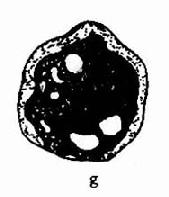

(四)精子形态(见图11-1)

通常用于精子形态学检查的方法的有两种,一种是制成新鲜湿处副县长相差显微镜观察;加一种是将精子固定、染色后用亮视野光学显微镜观察。两处方法检查的精子形态无明显差别,染色后精子头可能稍有缩小。

1.正常精子形态检测政党精子形态的应遵循严格标准:①正常精子头部呈椭圆形,其正常标准为头部长度为4.0-5.5μm,宽为2.5-3.0μm,长与宽的比值为1.5-1.75项体区占头部的40-70%;②必须不存在颈、中段或尾部的缺陷;③细胞质微粒不大于正常头部的1/3;④将所的处于边沿异常状态的清子均列为不正常。

2.有缺陷精子:用这种形态学分析方法考虑的精子细胞功能部位,因此认为没有必要常规的去区分所有头部大小和形态之间可划或尾部缺陷之间的变异如果大多数精子细胞中出现某一种部位的异常,则应对这一普通的缺陷给予注释。需记录的缺陷有:

(1)头部形状、大小缺陷:包括大头、小头、锥形头、梨头、无定形头、空泡样头(头部大于20%区域出现不着色的空泡区、)双头或以上缺陷的联合体。

(2)颈、中段缺陷:包括缺尾可见到游离或脱落的头部,未附着或弯曲尾尾与头部长轴结呈90度角,肿胀、不规则、弯曲的中段,异常薄的中段无线粒体鞘或以上任何类型缺陷的联合体。

(3)尾部异常:包括短尾、多尾、发夹状尾、断尾、宽度不规则或卷尾、或尾部伴有末端微滴,或以上任何类型缺陷的联合体。

(4)细胞质微粒:大于正常头部的面积的1/3。细胞质微粒一般位于颈可中段部分,也有未成熟精子微粒沿尾部分而布在不同部位。

许多形态学的异常的精子有多种缺陷。当多种缺陷同时存在时,只记录一种,但应优先记录头部缺陷,其次为中段缺陷,最后为尾部缺陷。每种精子缺陷的平均数目称为畸形精子指数,是预测精子在体内、体外功能有意义的指标,因此形态学分析应该是多参数原,应分别记录每种缺陷。异常形态见图11-1。

精子形态

图11-1 精子形态

[临床意义] 正常精液中正常形态的精子应≥30%,精液中正常形态的精子减少称畸形精子症,与睾丸、附睾的功能异常密切相关。可见于生殖系感染。精南疆静脉曲张雄性激素水平异常时;某些化学药物(如硝基唪喃妥英)、遗传因素也可影响睾丸生精功能,导致畸形精子增多。